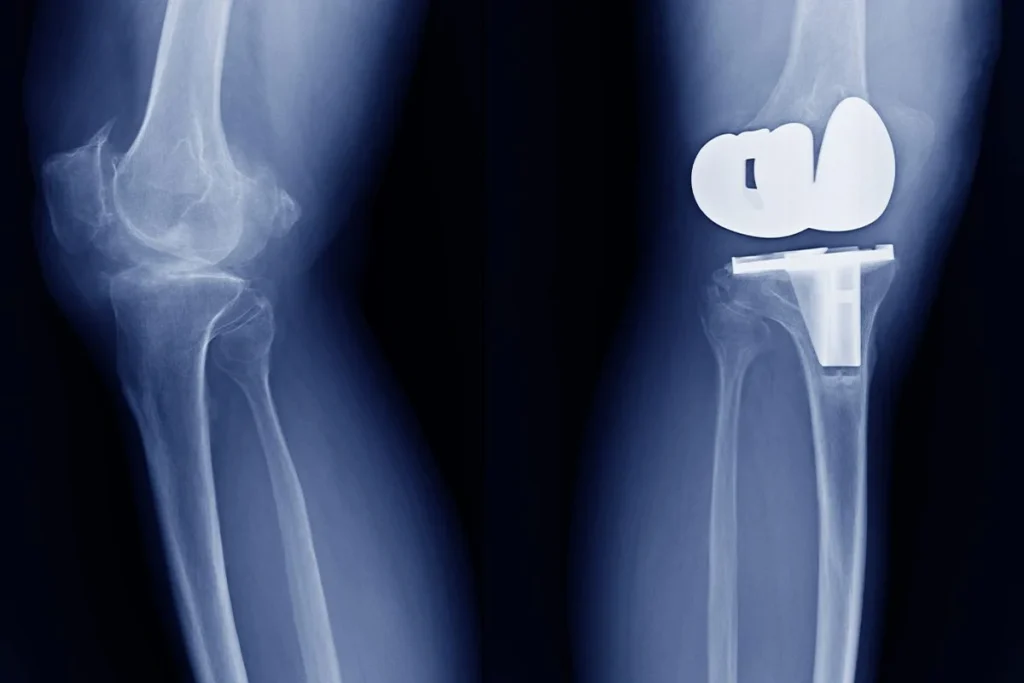

Cada año se realizan cerca de un millón de reemplazos de rodilla y cadera solo en Estados Unidos, unas intervenciones que devuelven la movilidad y calidad de vida a los pacientes. Sin embargo, en torno a un 2% de los pacientes sufre infecciones articulares periprotésicas, que es una grave complicación con difícil tratamiento.

Una vez que las bacterias se alojan en una parte del implante, los antibióticos son a menudo insuficientes, lo que lleva a ser necesaria la retirada de la prótesis y repetir la cirugía. Por este motivo, la comunidad médica lleva mucho tiempo tratando de desarrollar materiales que sean biocompatibles, resistentes y antimicrobianos.

Los reemplazos ortopédicos actuales suelen requerir una segunda operación después de 15-20 años. Cada cirugía de revisión tiene una mayor complejidad e implica mayores riesgos, y con este nuevo material, al conseguir integrarse mejor con el hueso y mantener alejadas a las bacterias, podría reducir de forma notable la necesidad de reintervenciones.